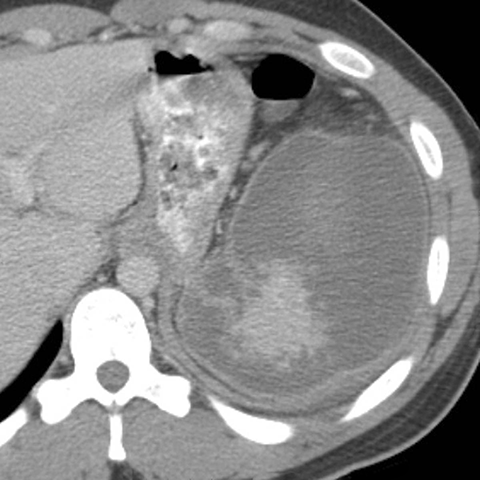

25-year-old male with mononucleosis presents with acute left upper quadrant pain